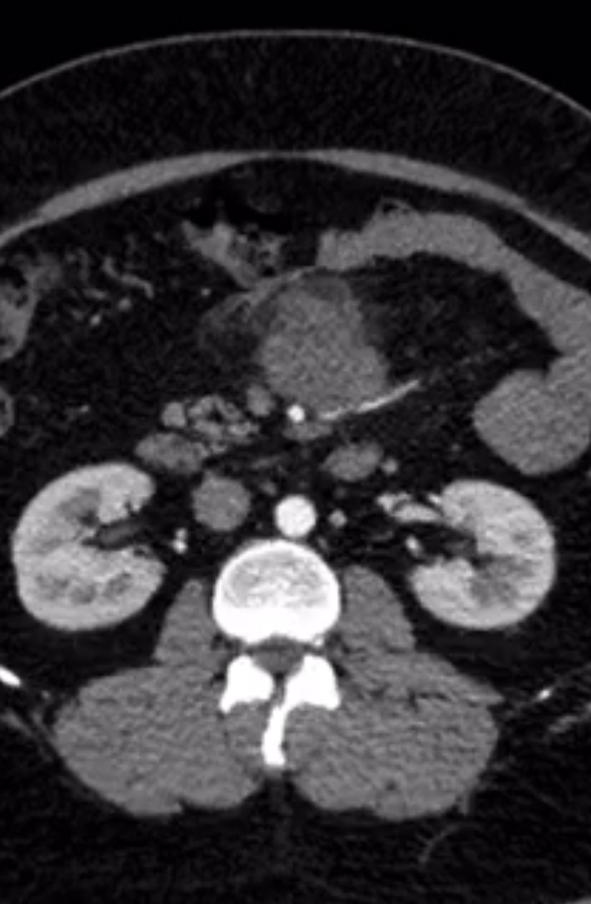

A 45 year old gentleman presented to us with vague abdominal pain. CT showed a large 6-7 cm tumor in the central mesentery sitting on important intestinal blood vessels. A CT guided biopsy proved it to be a sarcoma. The patient was obese but tumor seemed amenable for a laparoscopic surgery wherein the tumor was removed. Patient was discharged by 5th postoperative day.

Laparoscopic mesenteric surgery is ideal in small peripheral located tumors. However can be done even for large tumors close to major blood vessels as in our case depending upon surgeon experience.